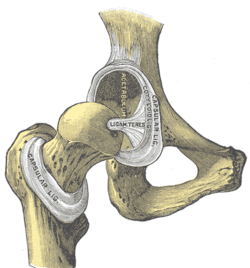

The hip joint is reinforced by four ligaments, of which three are extracapsular and one intracapsular.

The extracapsular ligaments are the iliofemoral, ischiofemoral, and pubofemoral ligaments attached to the bones of the pelvis (the ilium, ischium, and pubis respectively). All three strengthen the capsule and prevent an excessive range of movement in the joint. Of these, the Y-shaped and twisted iliofemoral ligament is the strongest ligament in the human body. [17] In the upright position, it prevents the trunk from falling backward without the need for muscular activity. In the sitting position, it becomes relaxed, thus permitting the pelvis to tilt backward into its sitting position. The iliofemoral ligament prevents excessive adduction and internal rotation of the hip. The ischiofemoral ligament prevents medial (internal) rotation while the pubofemoral ligament restricts abduction and internal rotation of the hip joint. [18] The zona orbicularis, which lies like a collar around the most narrow part of the femoral neck, is covered by the other ligaments which partly radiate into it. The zona orbicularis acts like a buttonhole on the femoral head and assists in maintaining the contact in the joint. [17] All three ligaments become taut when the joint is extended - this stabilises the joint, and reduces the energy demand of muscles when standing [19]

The intracapsular ligament, the ligamentum teres, is attached to a depression in the acetabulum (the acetabular notch) and a depression on the femoral head (the fovea of the head). It is only stretched when the hip is dislocated, and may then prevent further displacement. [17] It is not that important as a ligament but can often be vitally important as a conduit of a small artery to the head of the femur, that is, the foveal artery.[20] This artery is not present in everyone but can become the only blood supply to the bone in the head of the femur when the neck of the femur is fractured or disrupted by injury in childhood.[21]